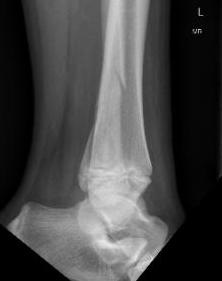

| SH I distal tibia / fibula | SH II distal tibia | SH III medial malleolus |

![]() |

| Low risk growth arrest | 40% risk growth arrest | 30% risk physeal bar |